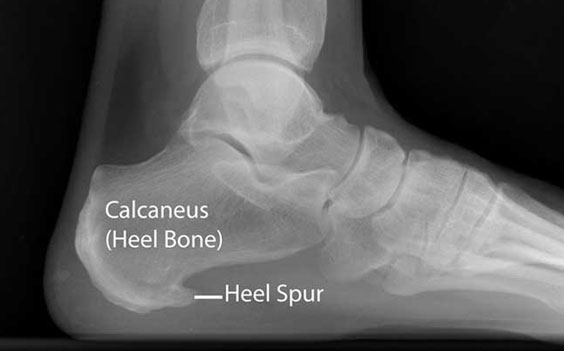

Heel spur

Pain, inflammation, or even a bony protrusion at the front of the heel may be symptoms of a heel spur. Heel spurs occur because of a calcium deposit that grows between your heel and arch.

Heel spurs may be diagnosed through the pain you feel in your heel or as a result of another foot condition altogether, such as plantar fasciitis. It may be difficult to diagnose this condition yourself.

You should rest your feet, evaluate your footwear, and see your doctor if you experience heel pain. Heel spurs can be treated with cold compresses, medications, physical therapy, and possibly surgery.